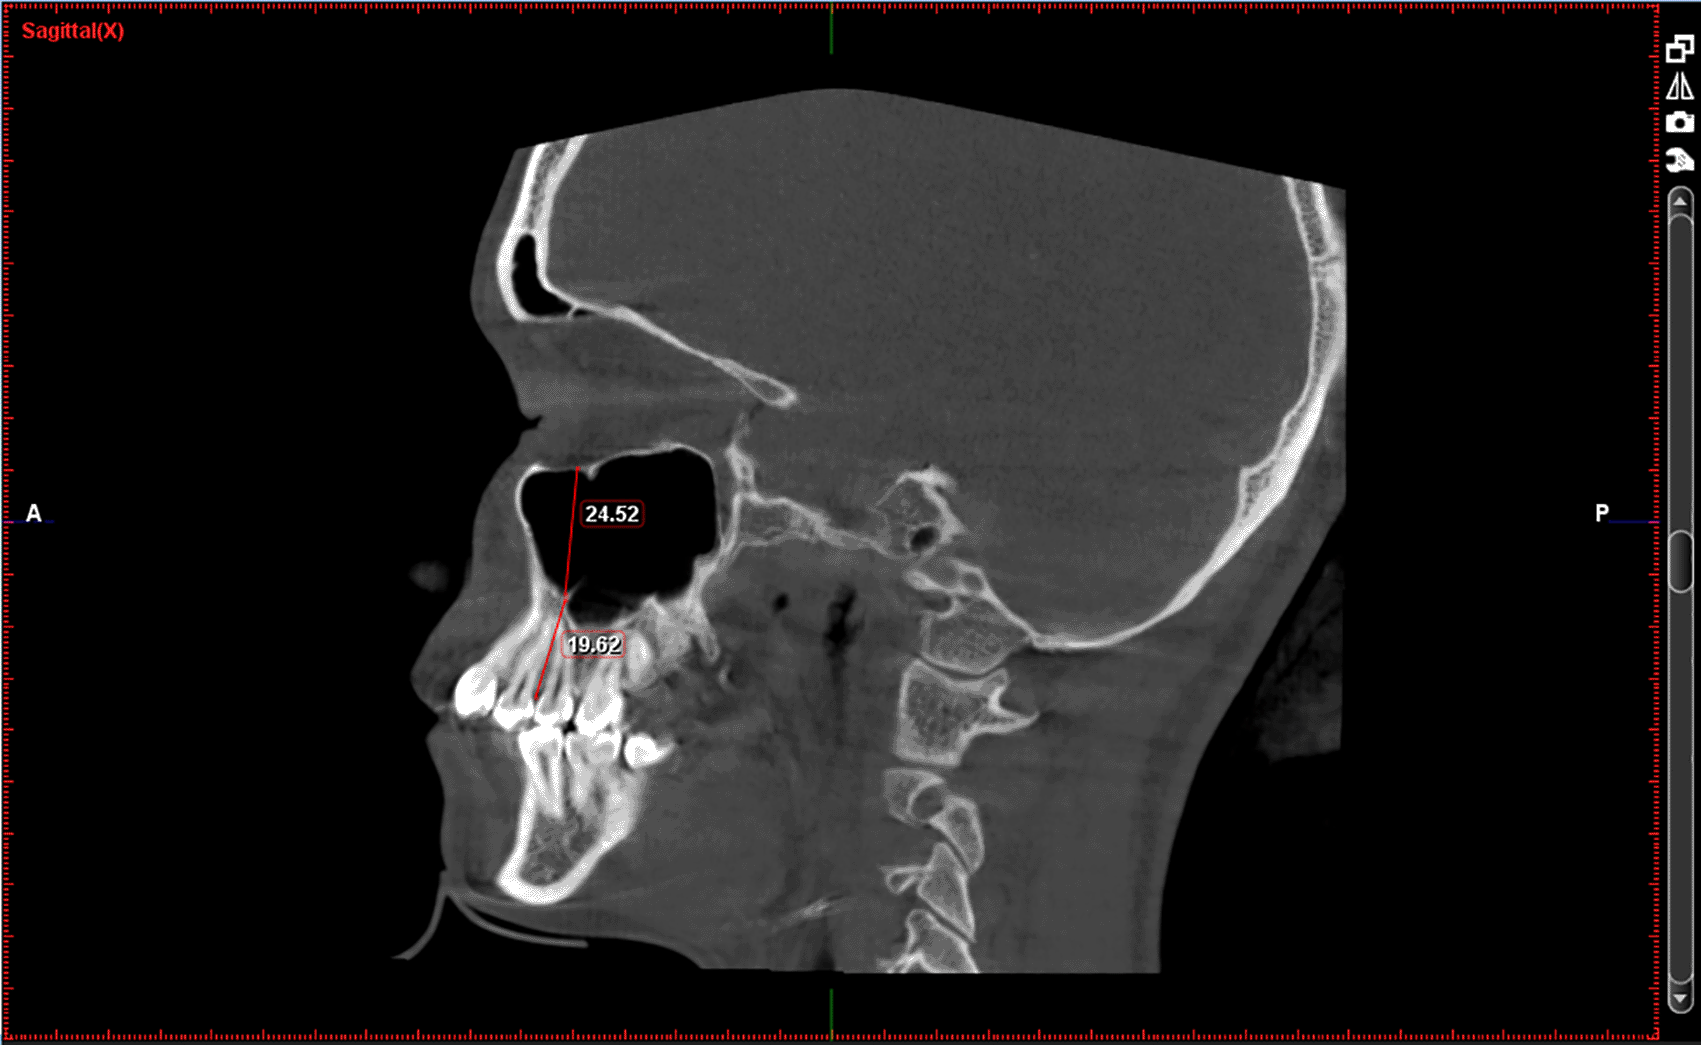

A total of 66 full FOV CBCT scans of patients satisfying inclusion and exclusion criteria were collected from the department archives. The CBCT images were previously obtained with patients written consent for diagnostic purpose using Planmeca ProMax Machine (230-240 V, 50 Hz, 16 A) manufactured by Planmeca OY (Helsinki Finland). The images were in DICOM file format and were analysed using Planmeca Romexis Viewer (Version 5.1.0.4). All the records were analysed by a single observer. Three locations were chosen to measure sinus height and basal bone height: PM1-PM2(between premolars), PM2-M1(between 2nd premolar and 1st molar), M1-M2(between molars).

Following measurements were recorded bilaterally and mean value was obtained; Figures: 1-3

1. Height of the maxillary sinus

2. Basal bone height